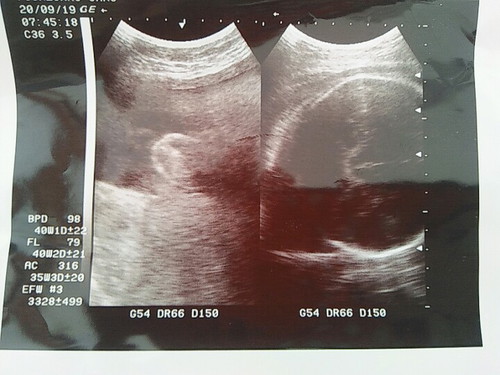

USG

Bantu jawab, itu Usia kehamilaannya udah 40mgg lbih yaah.. taksiran BB janin 3328 gram. Cm itu yg usa dibaca dri tulisannya